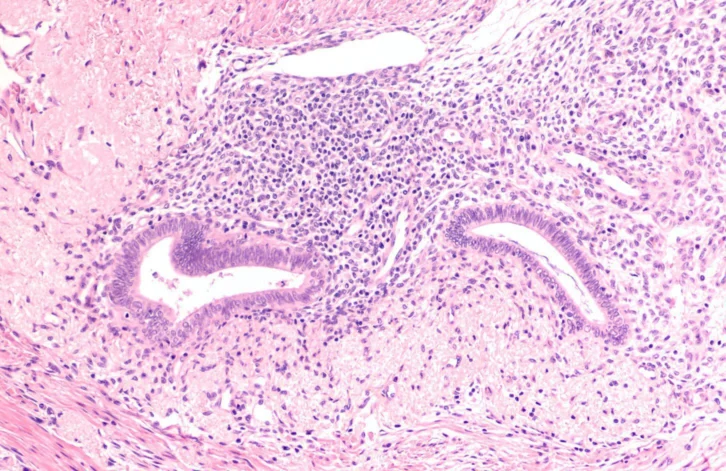

Cyclana Bio has demonstrated the role of the extracellular matrix (ECM) in endometriosis, where disregulation of the ECM causes inflammation and loss of tissue function. Until now, drug development strategies to treat endometriosis have focused on intracellular mechanisms, failing to target the interaction between cells and the ECM, and have resulted in sub-optimal treatment efficacy.

The startup is focused on building whole tissue models of disease, harnessing menstrual fluid and lab-based modelling. It is hoped this approach will uncover early biomarkers of disease and identify novel targets for drug development.